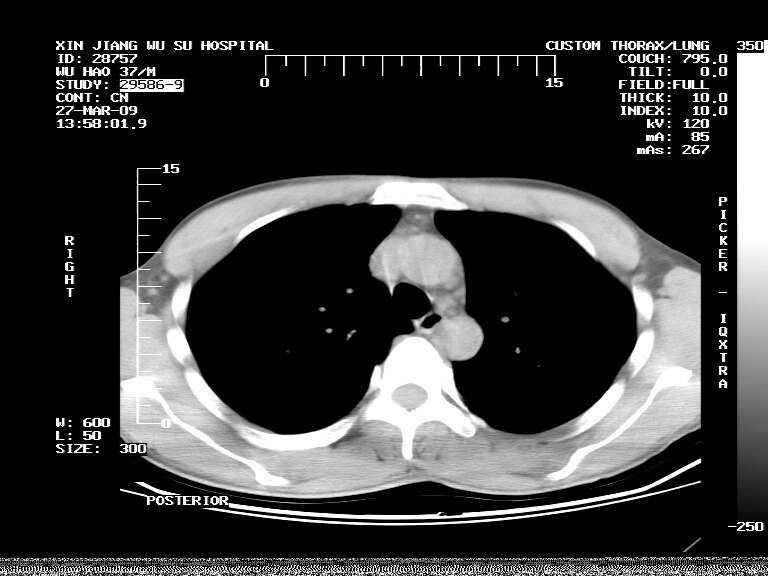

男,37岁,体检胸透发现阴影。

患者体检发现 无症状 左肺下叶占位,边缘模糊,可见血管聚束、分叶、胸膜牵拉,增强呈不均匀性强化。 首先考虑左肺下叶周围型肺癌,建议穿刺活检。

患者体检发现 无症状 左肺下叶占位,边缘模糊,可见血管聚束、分叶、胸膜牵拉,增强呈不均匀性强化。 首先考虑左肺下叶周围型肺癌,建议穿刺活检。支持!

左肺下叶见一结节病变,边缘欠清不光滑,与胸膜粘连且胸膜局限性增厚,注药后呈环形强化,动脉期壁呈明显点环状强化,静脉期壁强化减低,中心密度低无强化,灶周无明显的卫星灶和水肿区(晕征)---考虑周围性肺癌,不除外感染性病变,建议穿刺活检。

左肺下叶软组织病灶,密度较高,内见点状钙化,其周围见子灶,邻近胸膜扁平样增厚.c+病灶强化明显,中心强化弱.诊断:左肺下叶结核瘤.